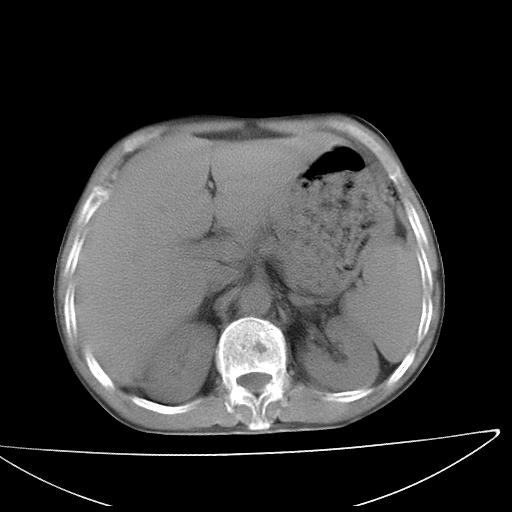

男  70岁,发烧咳嗽4天。盗汗,消瘦。无痰中带血丝,以前有肺tb病史,ct见,双肺tb,左侧胸廓塌陷,左胸膜肥厚粘连。纵隔移位,右侧胸腔积液,大家说说那个心影前左肺舌叶除了肺大炮还有炎症还是干酪性肺炎?有占位吗?我看纵隔淋巴结也大。

是胃,纵膈未见明显肿大淋巴结。

1)两肺继发性肺结核并左肺上叶肺不张,支气管扩张。2)双侧胸膜炎(胸膜增厚+少量胸腔积液)。

两肺继发性肺结核并感染,左肺上叶肺不张。建议ct增强。